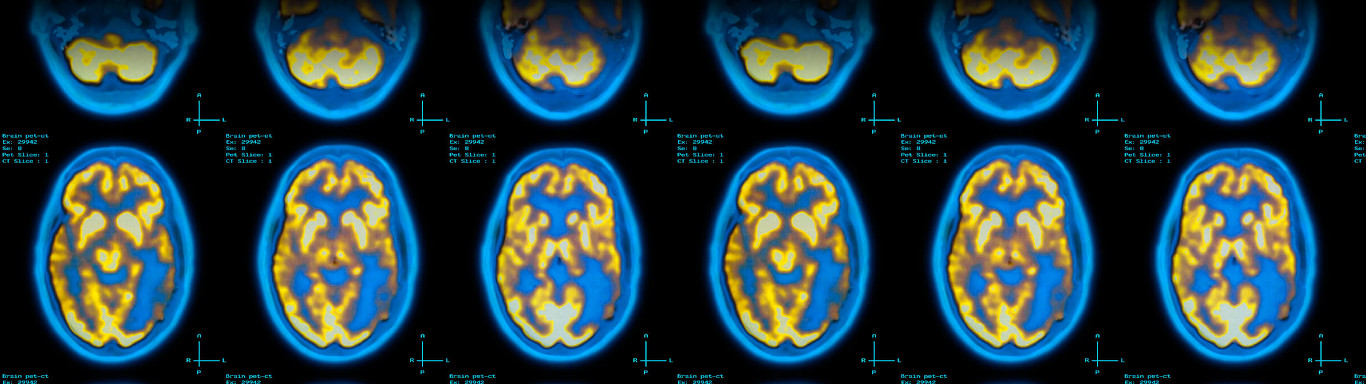

Initiation au traitement d'image

Course categoryMaster Biophysique et Imagerie fonctionnelle